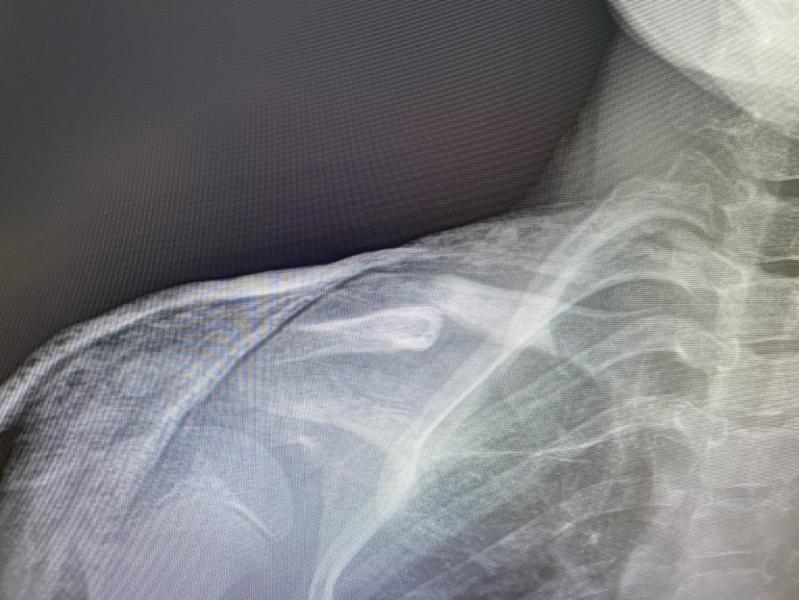

Третий раз были на рентгене. Косточки потихоньку сходятся. Гипс еще носить недели 2 точно. Потом 2 месяца восстановление. Никаких роликов. Коньков, скейтов. Можно только плавать, в июле будем на море, там поплаваем. То есть три месяца дочка будет без льда, без тренировок. В середине августа сборы, я оплатила, но пока добро на них не дали, врач сказал, что будет видно по факту. Вопрос: сколько денег мне готовить на подкатки , учитывая, что Варя столько пропустит? 🙃 кто выходил на лёд после трав...